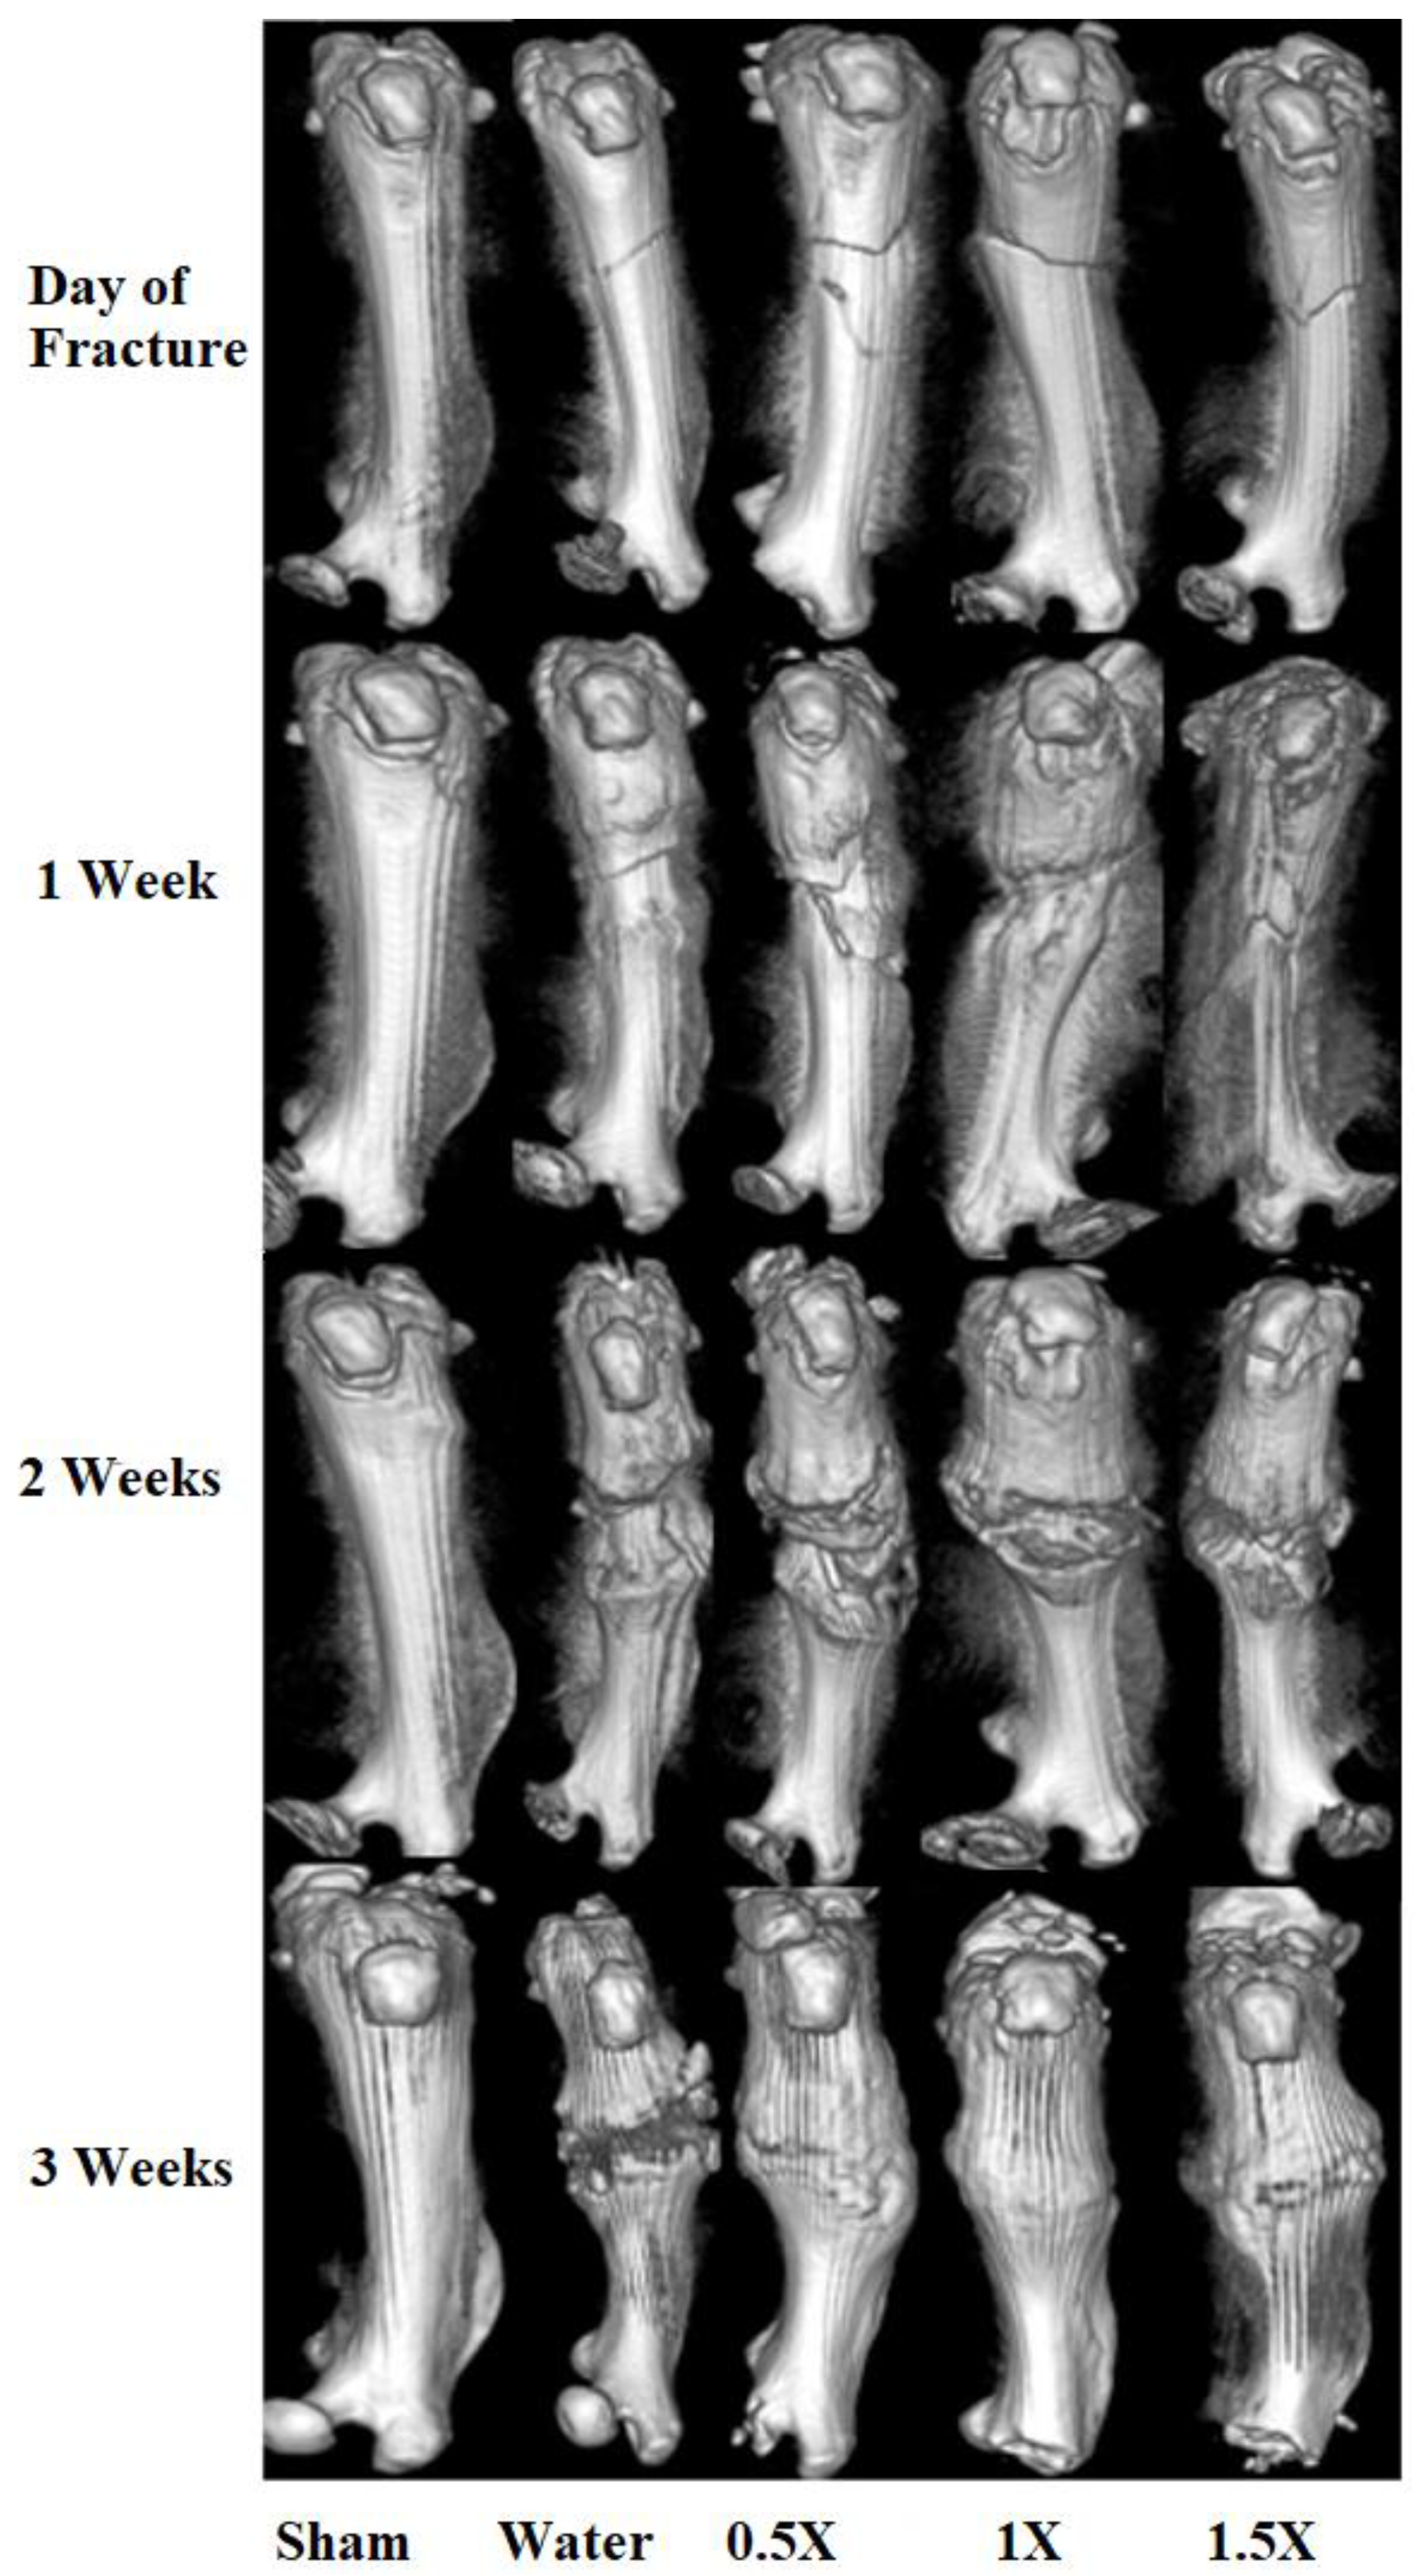

3.2. Radiological and Histomorphometry Results

3.3. Weight-Bearing Results